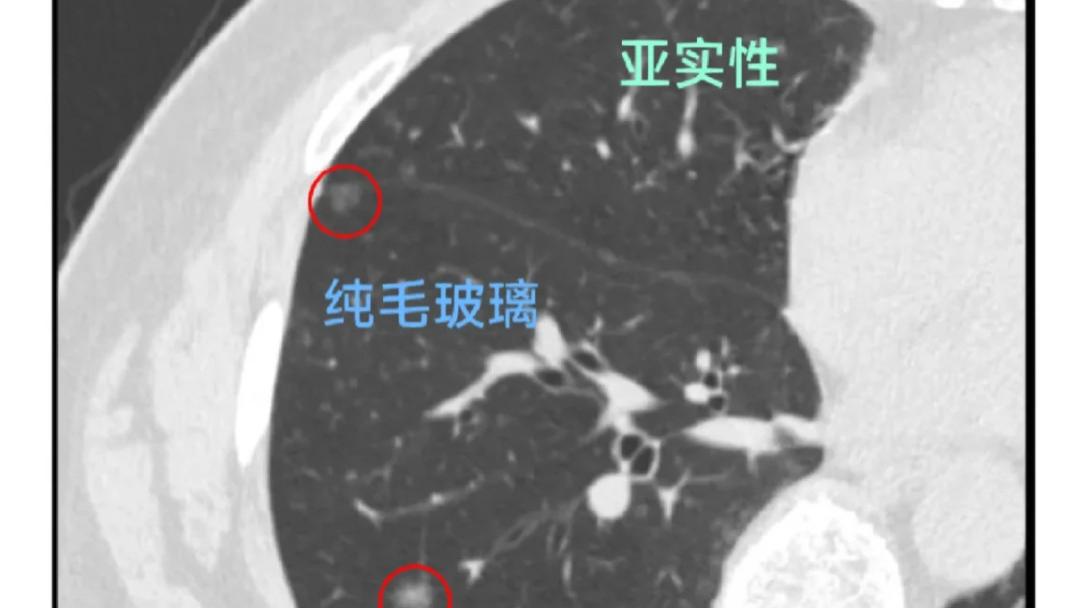

肺结节的4种恶性类型?如果肺CT不能判断结节性质,该怎样检测?如何康复?